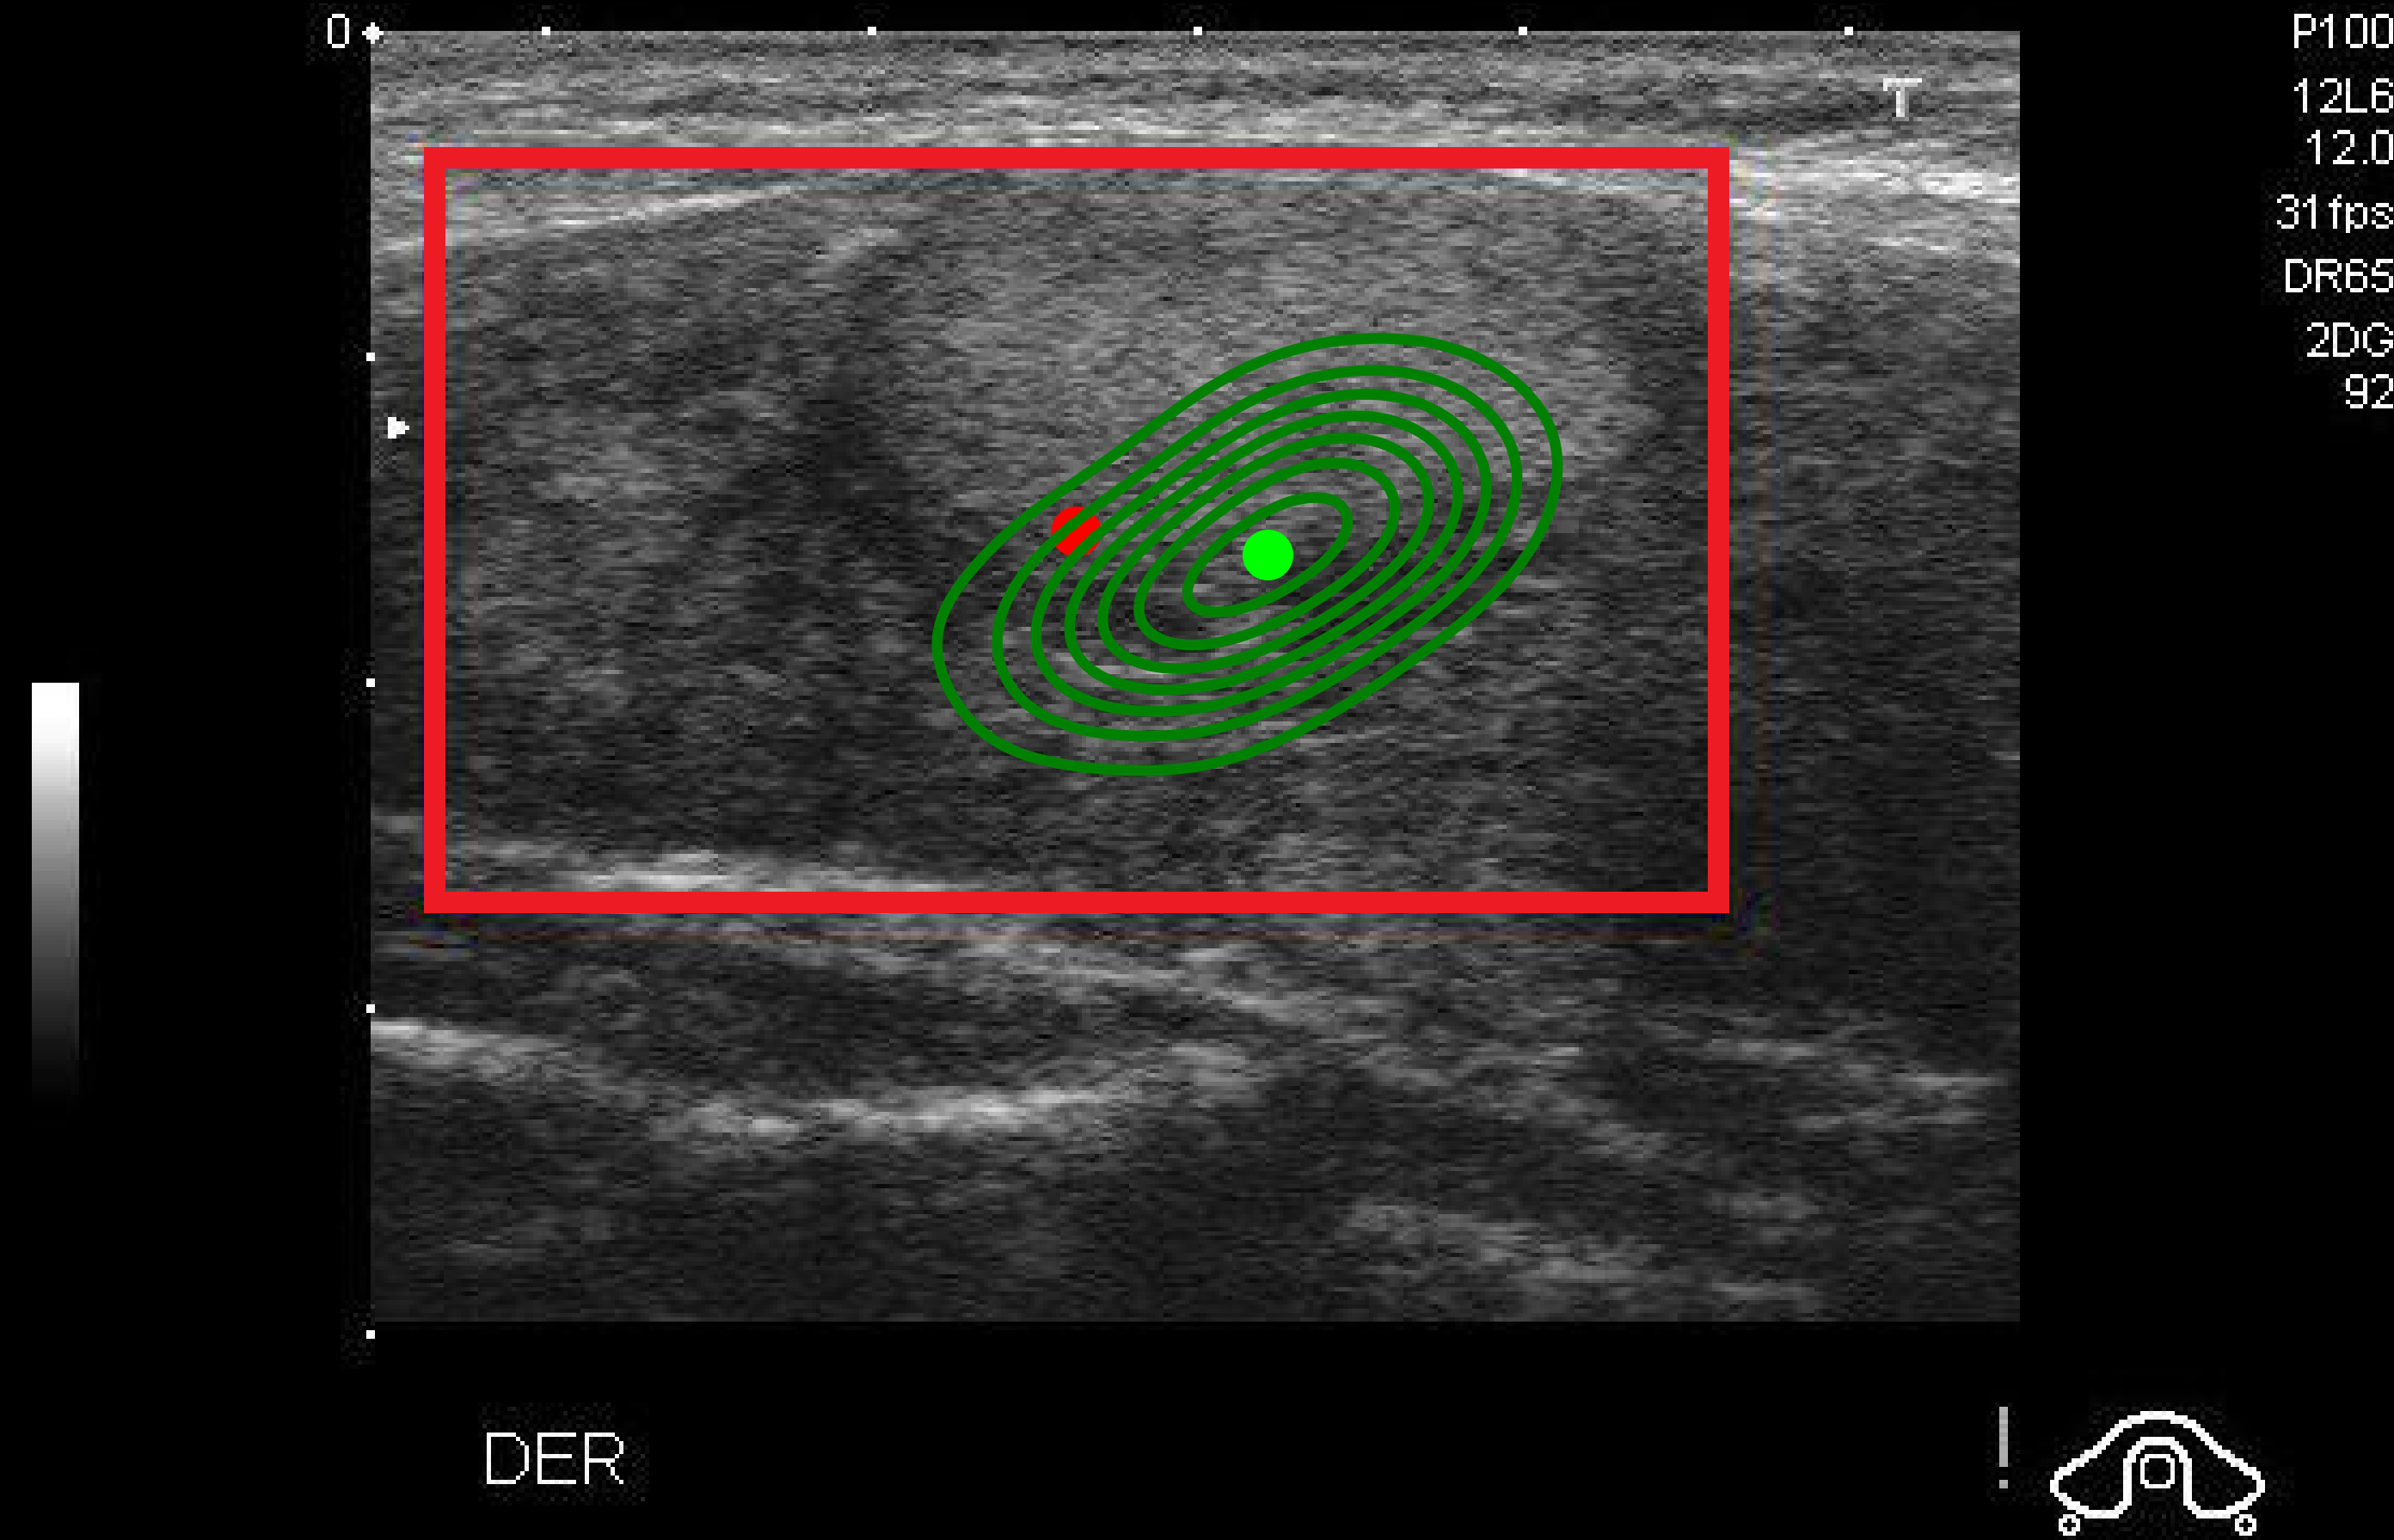

Density map (DM)

DM is commonly used in crowd counting context to estimate objects’ distribution in an image li2020density . We propose DM as a new statistic-based method in the context of XAI by extracting the frequency value of each pixel from boxes predicted by the model in region proposal generation, as shown in Fig. 4. The pixel’s frequency value is calculated by the number of boxes containing that pixel. For an input image , the model detected boxes after the first stage. For any box , let be the set of coordinates . Thus, DM’s output of is the matrix defined as , where is computed:

The more focused boxes a pixel has, the redder colors are indicated in the DM’s explanation. In Fig. 4a, the model detects two boxes containing nodules where the blue box is correct with the ground-truth label, while the red box is false. The DM’s saliency map can explain the blue box with redder colors, indicating that the model focuses on this region to detect the nodule.